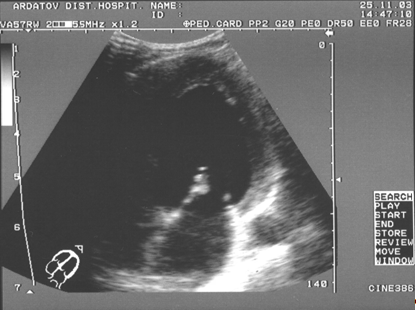

Секторальное сканирование митрального клапана обычно начинается по продольной оси из парастернального доступа и позволяет визуализировать обе его створки и сухожильные нити (рис. 3 - 4).

Рис. 3. В-эхограмма нормального митрального клапана в проекции длинной оси левого желудочка из парастернального доступа, диастола (собственное наблюдение).

Рис. 4. В-эхограмма нормального митрального клапана в проекции длинной оси левого желудочка из парастернального доступа, систола (собственное наблюдение).

В этом сечении можно оценить их структуру, подвижность и геометрию движения. У здоровых лиц эти образования выглядят относительно тонкими с ровными контурами и равномерными эхоструктурами. Эхоструктура створок митрального и трикуспидального клапанов в норме сопоставима. Во время диастолы митральные створки движутся в противоположном направлении, образуя две почти параллельные линии. Задняя створка при этом часто сливается с одноименной стенкой левого желудочка. В целом, процесс их открытия напоминает движение "утиного клюва". В систолу они образуют структуру, напоминающую вместе с хордами букву Y, где створки - ветви, а хорды - "нога".